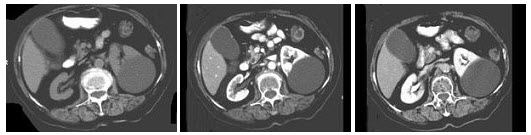

5、单项选择题

根据所提供的图像,该患者的最可能的诊断为直肠()

A.直肠静脉曲张

B.直肠癌

C.直肠息肉

D.直肠淋巴瘤

E.直肠炎症